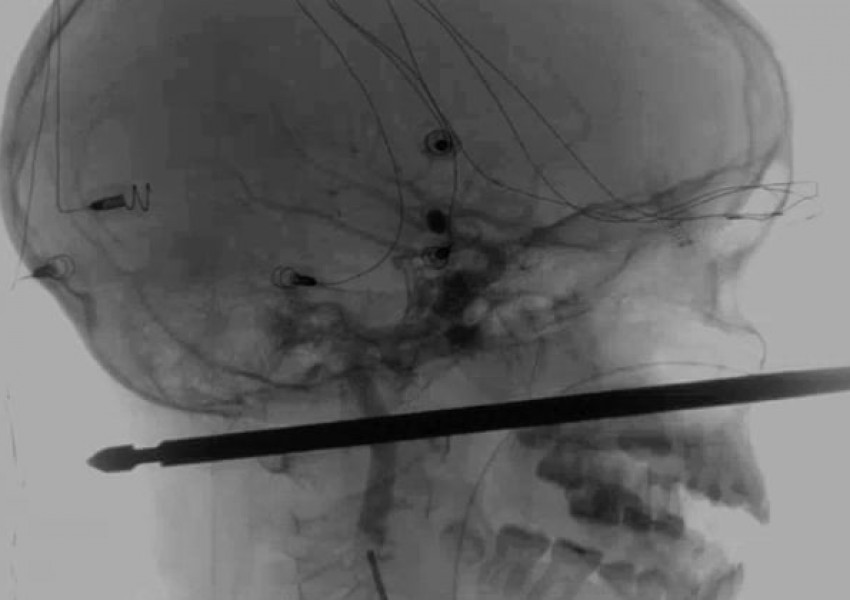

Шиш мина през главата на американче, то оцеля

Американче на 10 години оцеля, след като падна върху шиш за месо, който премина през главата му от лицето до тила, съобщи Асошиейтед прес. Лекарите нарекоха оцеляването на Зейвиър Кънингам "чудо". Зейвиър паднал върху шиша, след като...